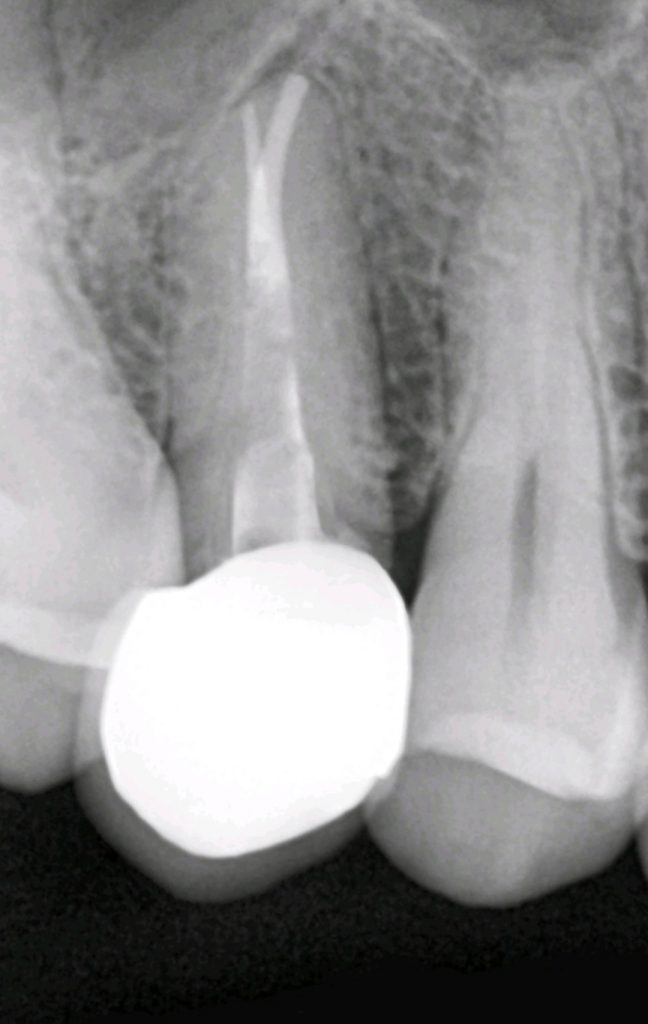

for the treatment plan, firstly we decided to focus on chief complain and perform a root canal treatment (the tooth had one root canal with very deep apical split which is challenging ) but we successfully shaped ,cleaned and filled it using CLC with bioceramic sealer.

Then we made a fiber post .